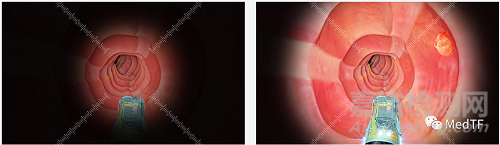

Saneso 360°主要?jiǎng)?chuàng)新在于其擁有五個(gè)攝像頭,因此提供了一個(gè)前所未有的 360°胃腸道視圖。通過(guò)主機(jī)主機(jī)中的360 Workflow Management軟件可以輕松直觀地呈現(xiàn)圖像解釋。Saneso 360°創(chuàng)新的前視、側(cè)視和后視攝像頭可以看到胃腸道的褶皺和轉(zhuǎn)彎背后。

Saneso 360°采用最先進(jìn)的長(zhǎng)效 LED。Select Band Imaging能夠在窄譜范圍內(nèi)檢查胃腸道。Dual Band Imaging可以允許醫(yī)生靈活地在白色和窄光譜下同時(shí)檢查胃腸道。